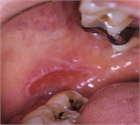

1. 口腔の粘膜疾患は口腔粘膜に症状を呈する病変の総称であり、その中にはさまざまな病変が含まれる。口腔粘膜に限局した疾患、顎顔面領域における病変が波及して口腔粘膜症状を呈したり、自己免疫疾患、内科疾患、皮膚疾患の部分症状が口腔粘膜に出現することもある。口腔粘膜に発現した疾患の鑑別診断により、全身性疾患が発見されることを加筆した。

1. 口腔の粘膜疾患は口腔粘膜に症状を呈する病変の総称である。

1. 口腔の粘膜疾患は口腔粘膜に限局して発現する病変のほかに、内科疾患、自己免疫疾患、皮膚疾患などの部分症状として口腔粘膜に病変が出現するものがある。